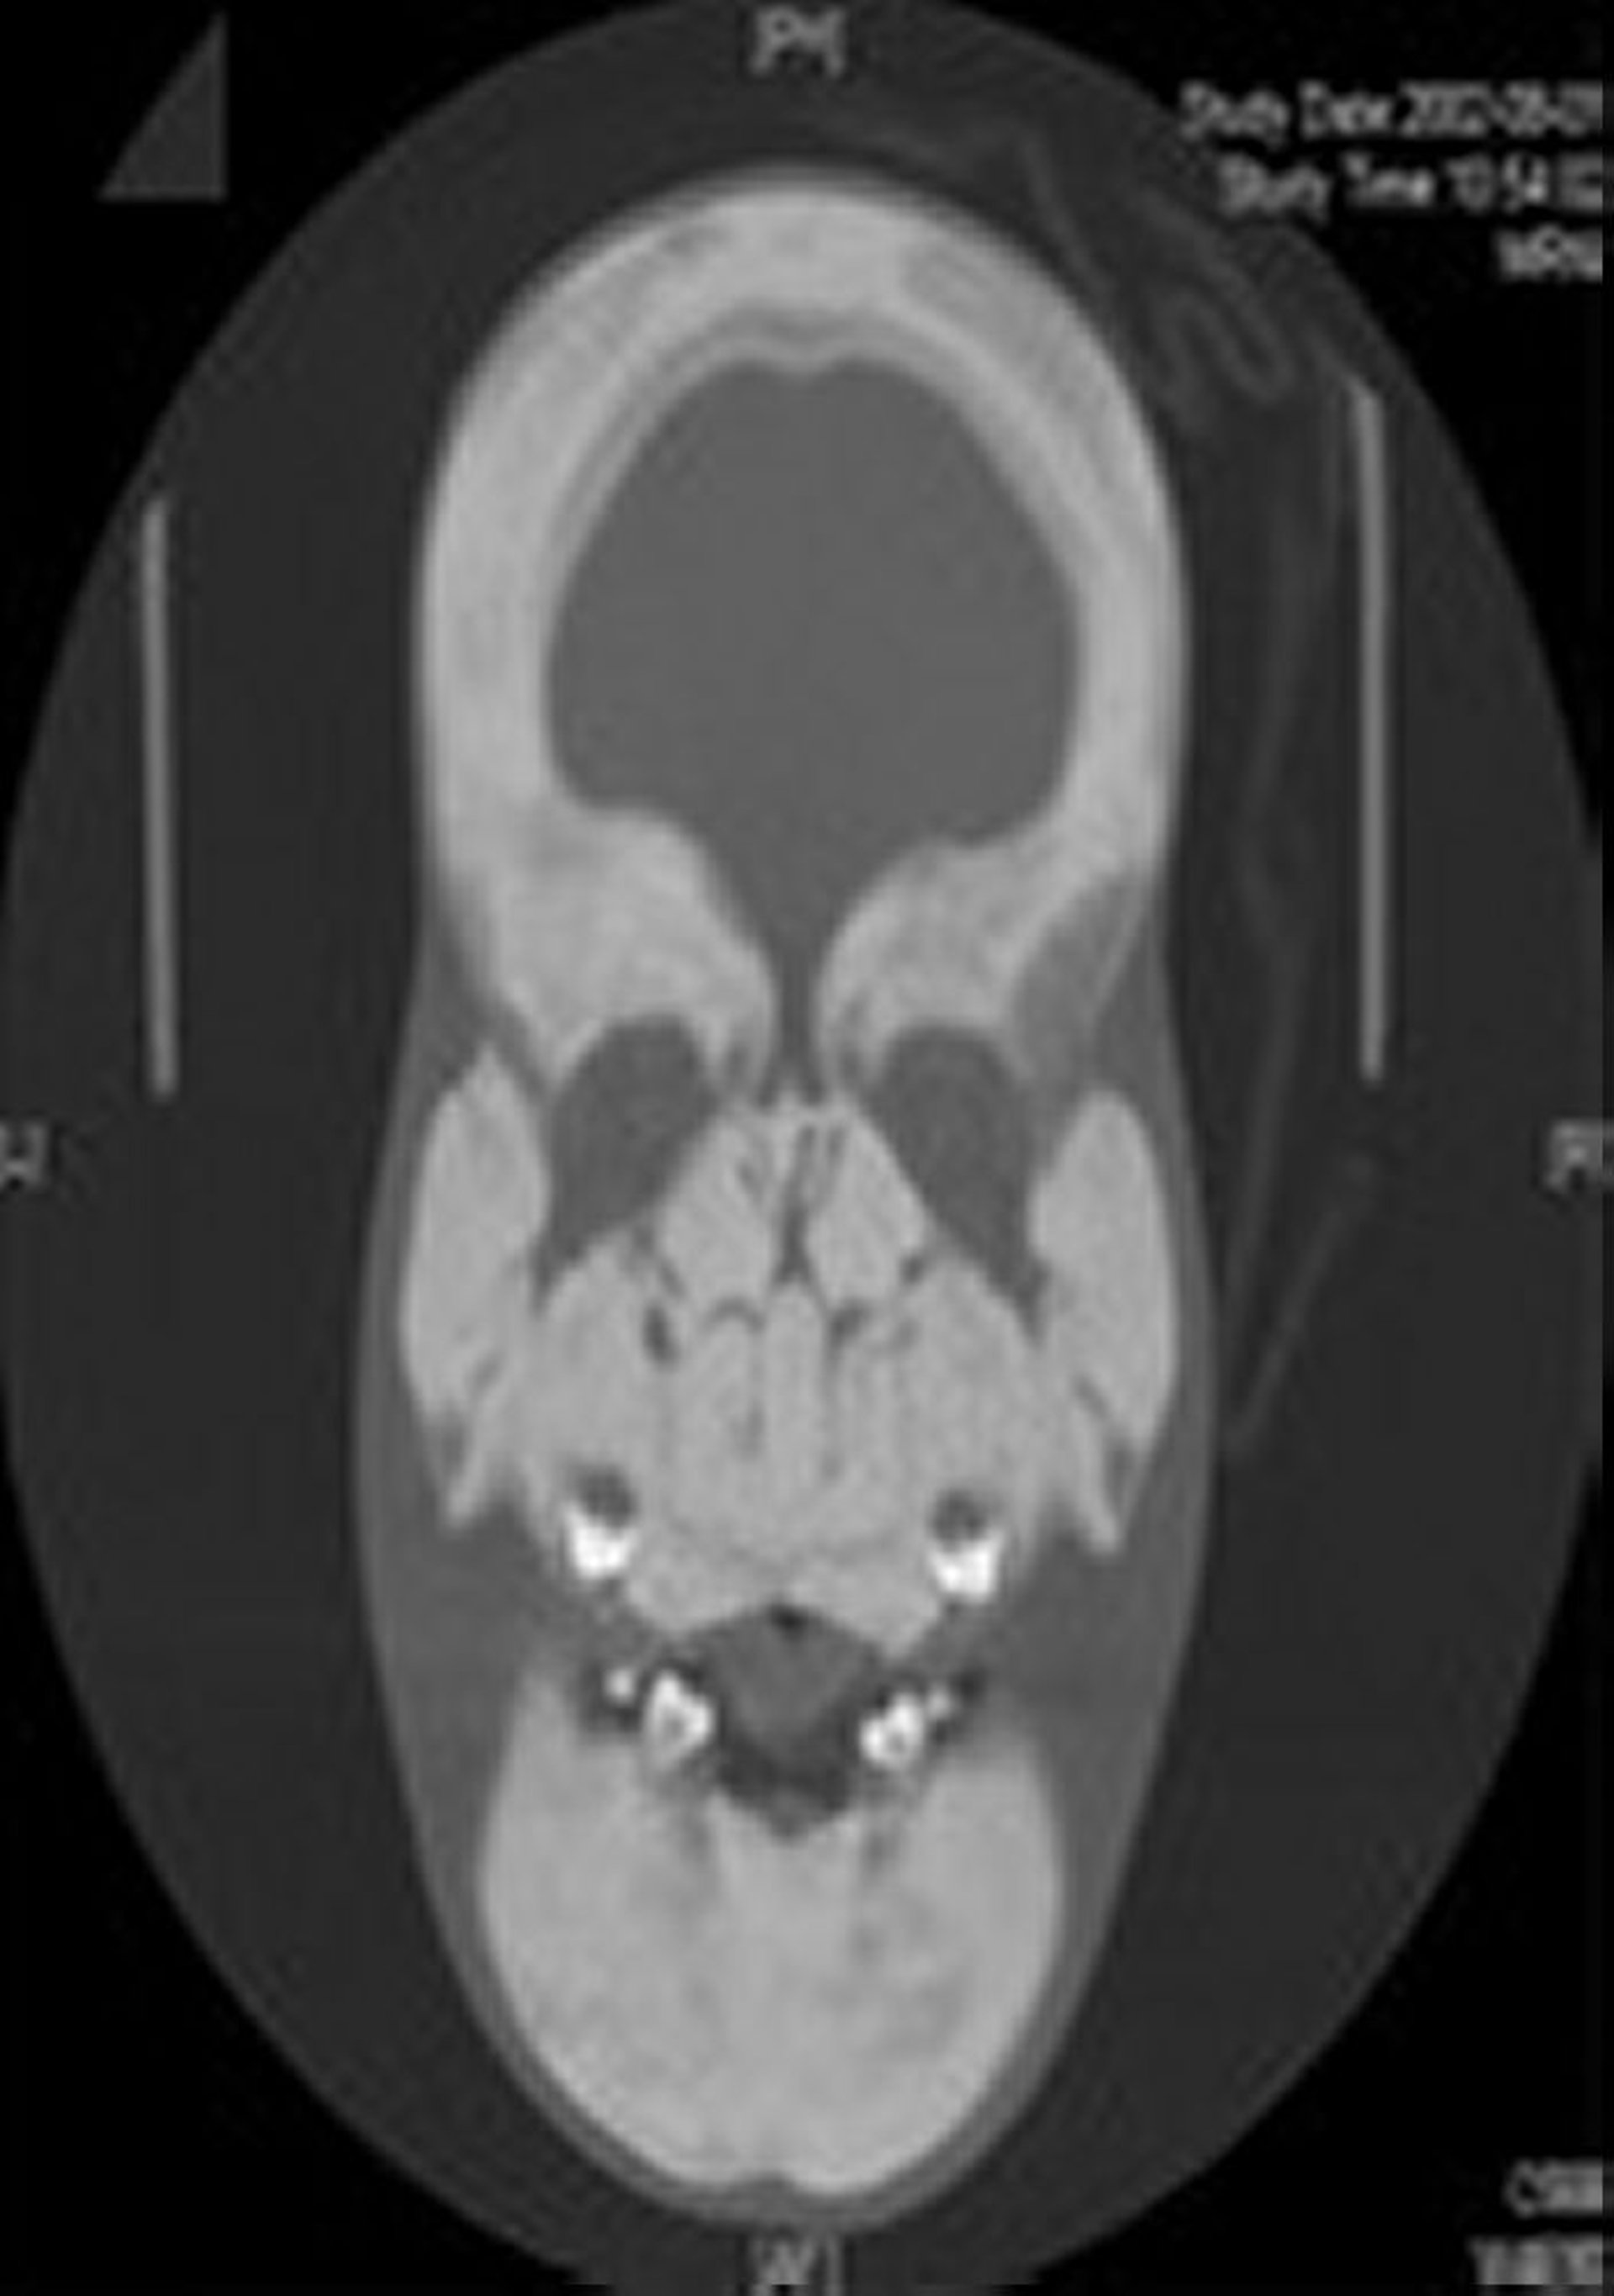

Esclerosteosis (radiografía)

Esta radiografía muestra un marcado engrosamiento y esclerosis del cráneo y todos los huesos faciales.